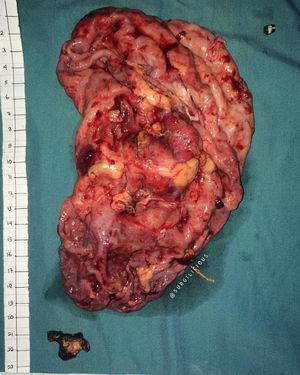

Hydronephrosis and its kidney stone

The average size of an adult human kidney is about 10 to 13 cm (4 to 5 inches) long, approximately 5 to 7.5 cm (2 to 3 inches) wide and about 2 to 2.5 cm (1 inch) thick.